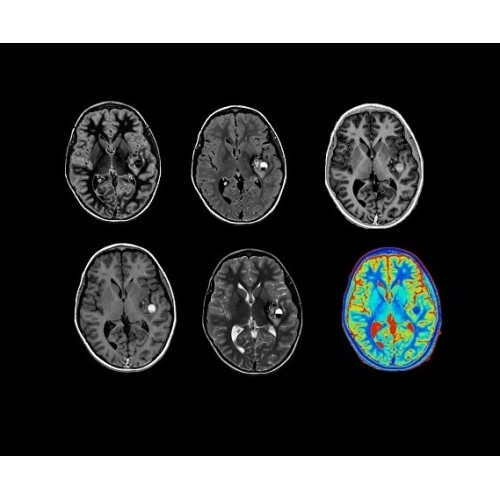

Стандартный пакет приложений SIGNA Works позволит вам достичь желаемых результатов в клинической практике благодаря набору высокоэффективных средств визуализации. Программные приложения, входящие в состав данных клинических пакетов, включают широкий спектр контрастов, функции обработки 2D- и 3D-данных, а также возможность коррекции артефактов движения. SIGNA Works предоставляет набор инструментов, необходимых для проведения эффективного клинического исследования.

• NeuroWorks — универсальное решение для визуализации анатомии головного мозга, позвоночника, сосудов и периферических нервов с четкой дифференциацией тканей.

• HyperWorks — пакет програмных приложений, который включает технологию HyperSense для поразительной визуализации и скорости.

• ImageWorks — повысит производительность МРТ благодаря визуализации высокого качества с MAGIC, четкими результатами пост-процессинга с READYView.